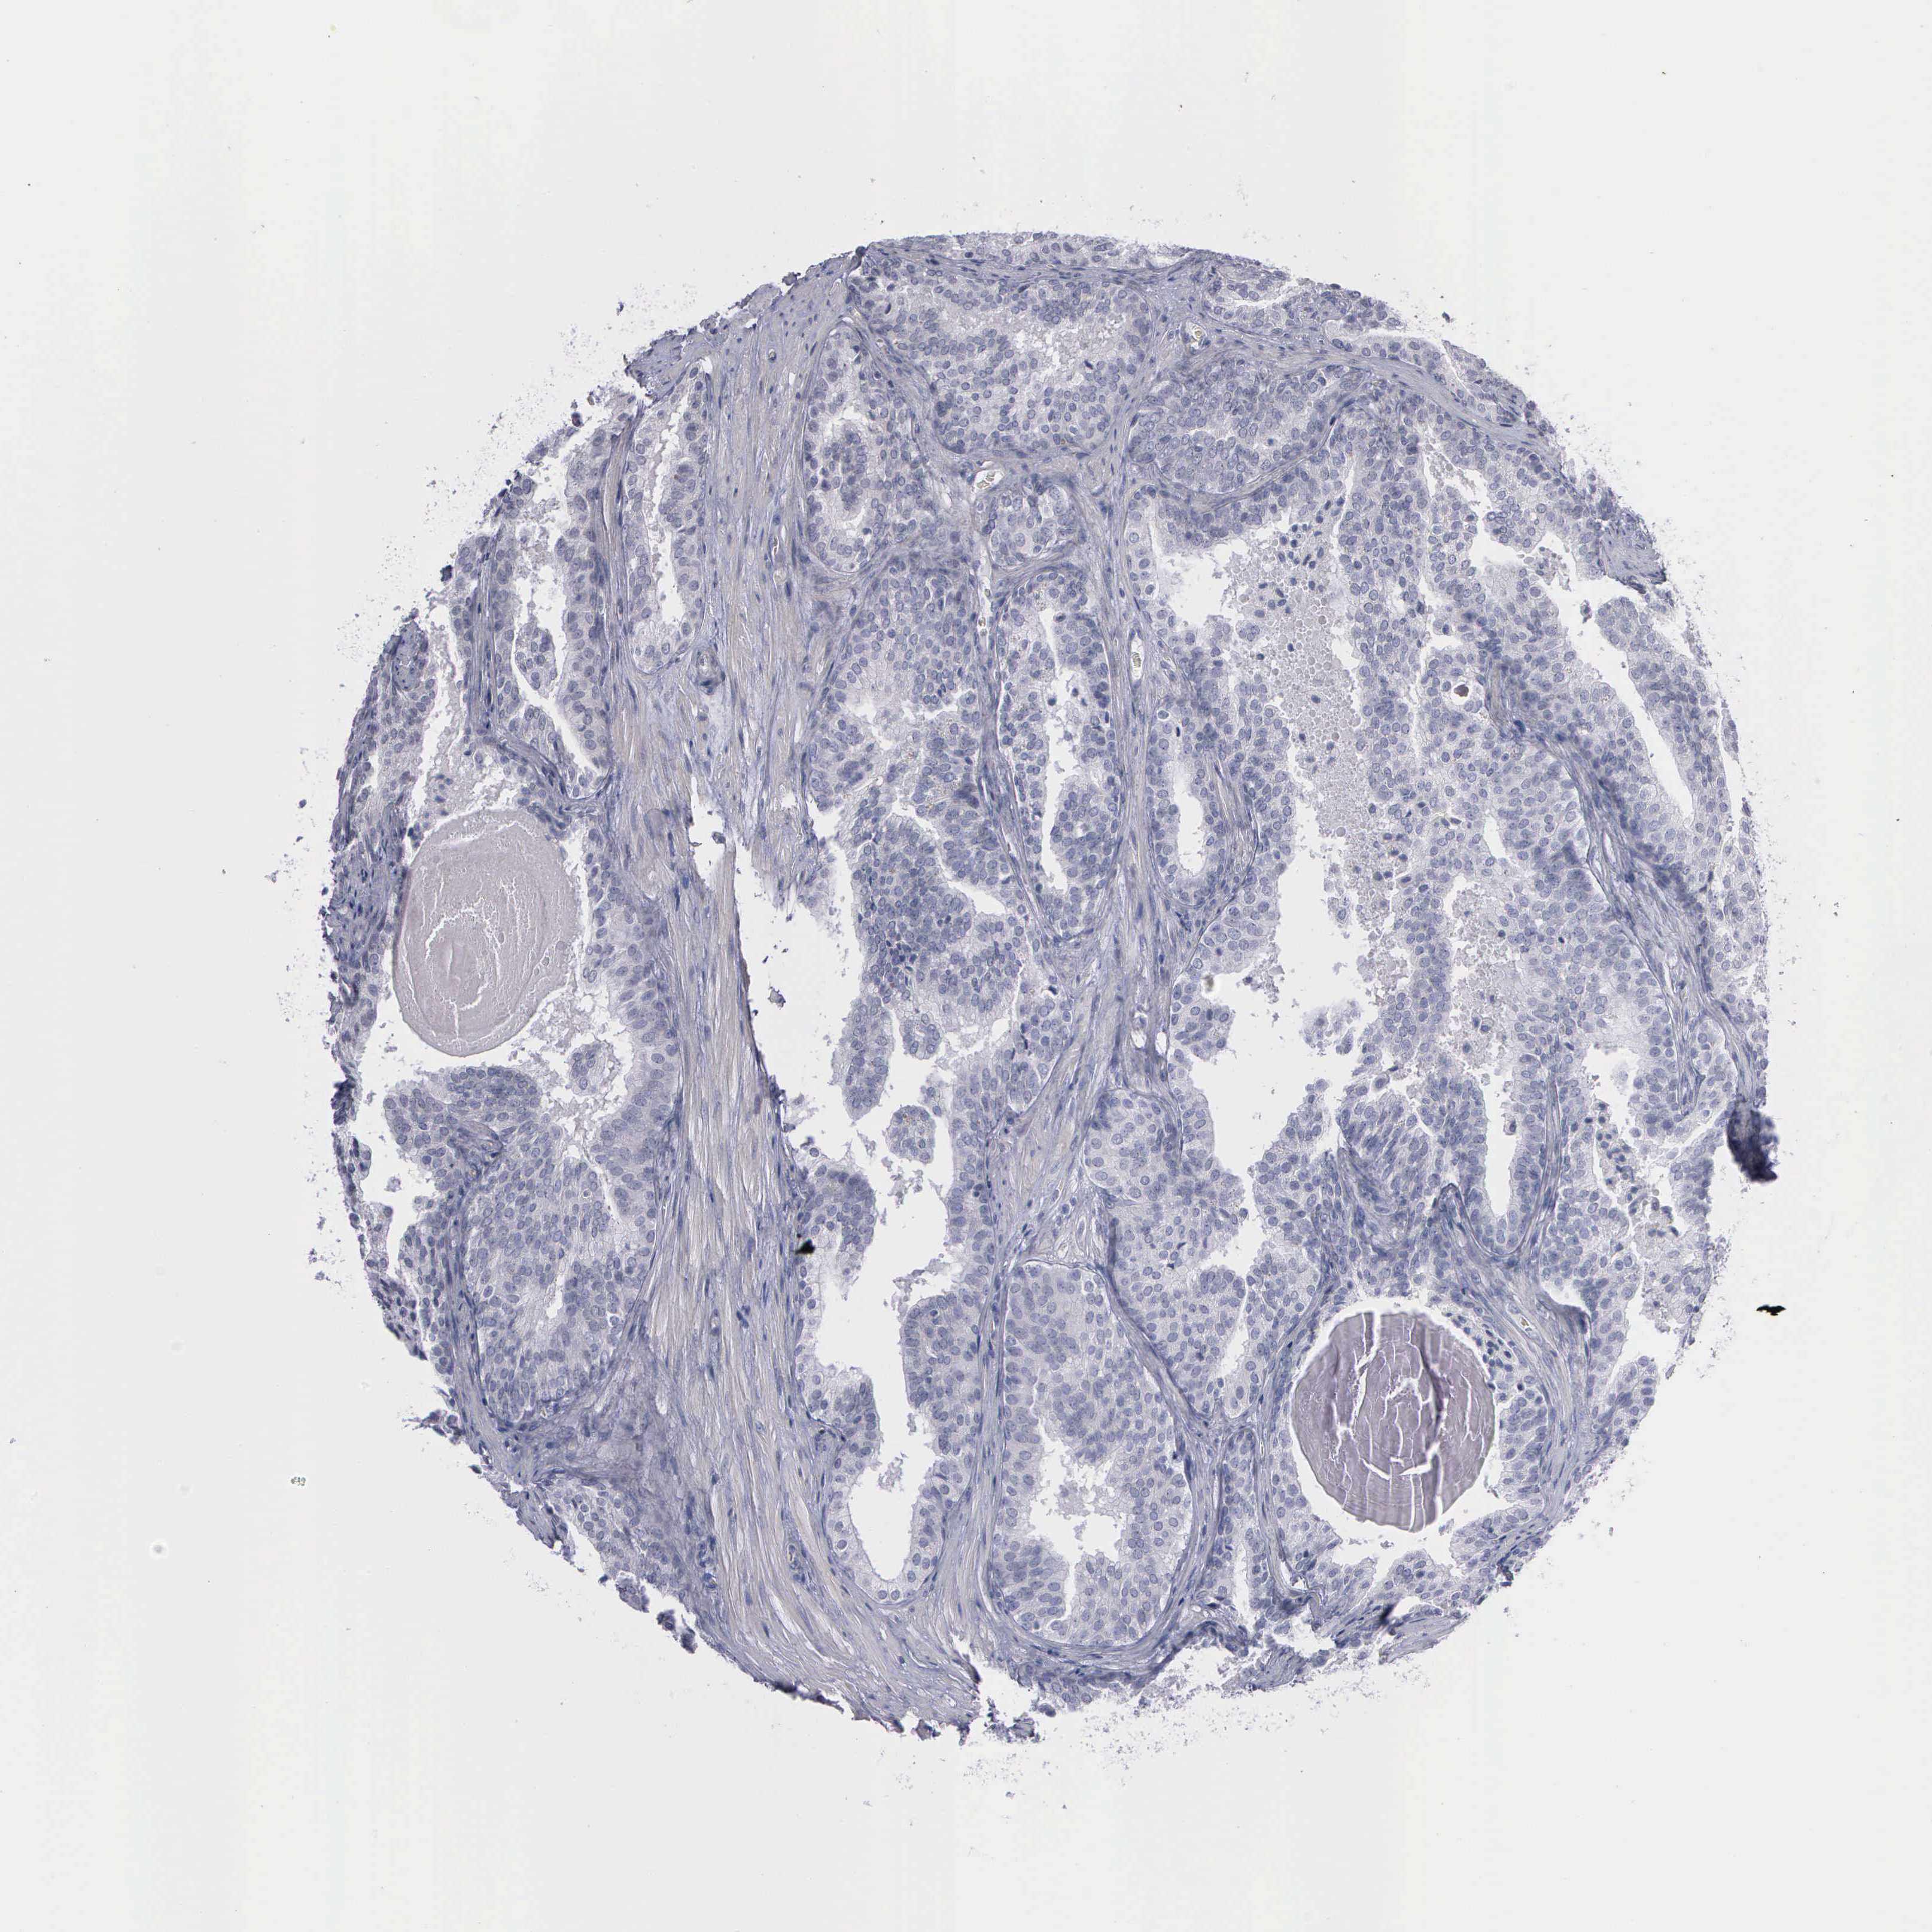

PROSTATE CANCER - Protein expressioni

A mouse-over function shows sample information and annotation data. Click on an image to view it in a full screen mode. Samples can be filtered based on level of antibody staining by selecting one or several of the following categories: high, medium, low and not detected. The assay and annotation is described here.

Note that samples used for immunohistochemistry by the Human Protein Atlas do not correspond to samples in the TCGA dataset.

Antibody stainingi

Antibody staining in the annotated cell types in the current human tissue is reported as not detected, low, medium, or high, based on conventional immunohistochemistry profiling in selected tissues. This score is based on the combination of the staining intensity and fraction of stained cells.

Each image is clickable and will lead to virtual microscopy that enables deeper exploration of all samples and also displays staining intensity scores, fraction scores and subcellular localization as well as patient and tissue information for each sample.

Adenocarcinoma, High grade

Adenocarcinoma, NOS

Adenocarcinoma, Low grade

Adenocarcinoma, Medium grade